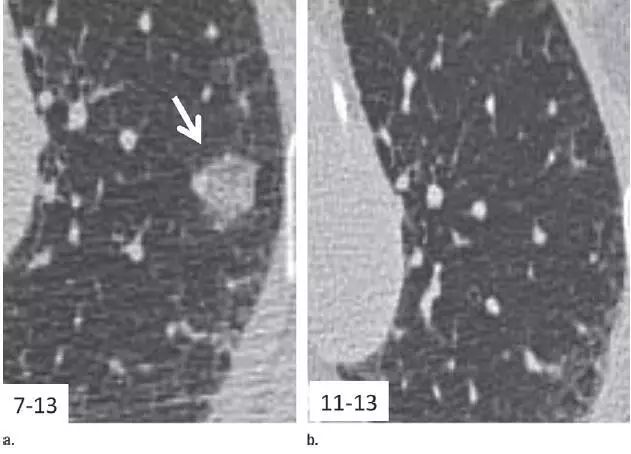

13. 相隔 3 个月的结节渐进表现

图 13(a)右肺下叶上段层厚 1 mm 的 CT 横断面图像,显示一个高度可疑(较大、磨玻璃样外观和实性形态)的部分实性结节(箭头)。(b)3 个月后的 CT 随访图像显示,实性成分的大小逐渐增加。手术显示为浸润性腺癌。